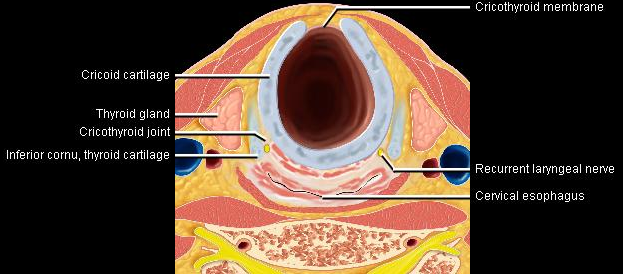

Phonation and dysphagia involve multiple coordinated structures in the larynx and pharynx. Radiation induced dysphagis appears to be related to dose to the phyaryngeal constrictor muscles and specific regions of the supraglottic and glottin larynyx.

Speech is impacted by doses to the epiglottis, base of tongue, aryepiglottic folds, false vocal cords upper esophageal sphincter and cricoid cartilage.